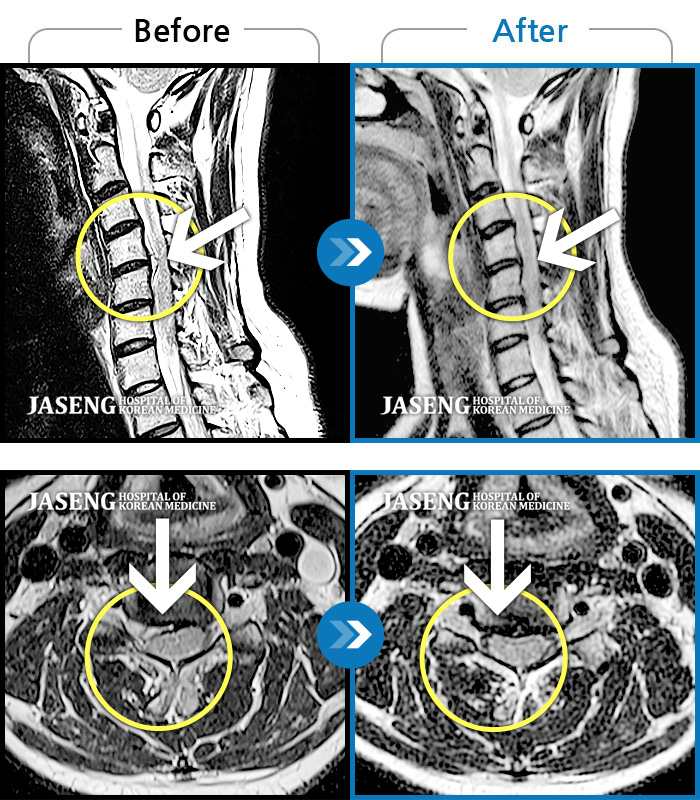

MRI 치료사례

오른팔을 거의 올리지 못하고 목과 팔 통증 극심